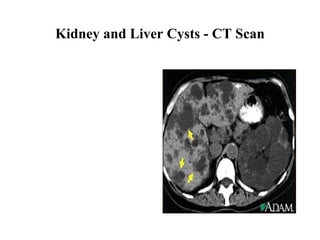

On the left is a CT scan through the abdomen of a patient with two enormously enlarged cyst-filled kidneys (shaded pink in the diagram below). To the right is shown a normal kidney in another patient. CT scans show a 'slice' through the body - here taken a fewcentimetres above the umbilicus.